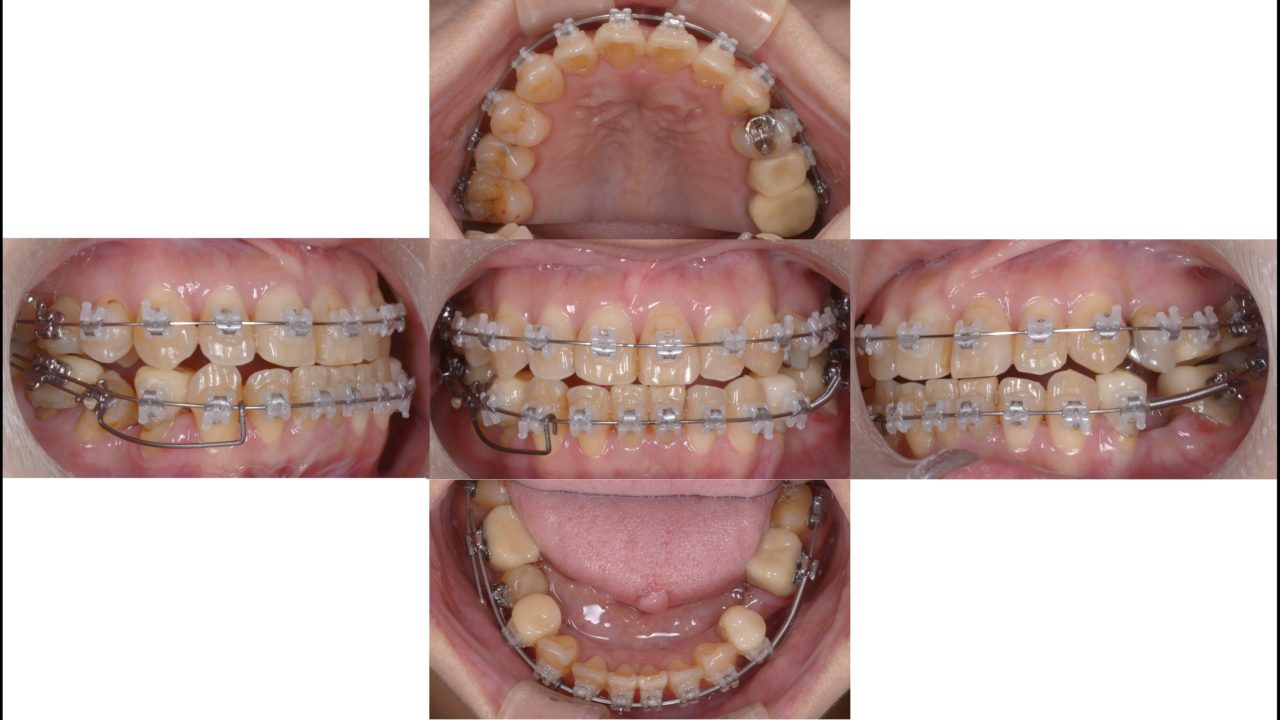

矯正治療開始 2018.9.4

矯正開始6か月 2019.3.18

右下第2小臼歯をアップライト